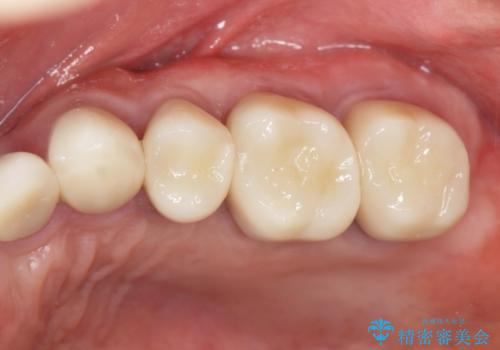

虫歯の徹底的な除去やセラミック補綴、精密根管治療、歯周外科を行うことで、治療後に歯磨きがしやすく、かみやすい機能的な仕上がりへと導きます。

- 63.8万円(ジルコニアクラウン×4・仮歯×4・歯周外科) (上顎左側臼歯4本分の費用)費用は治療当時の料金となります

歯周外科手術をおこなったことでフェルールも獲得でき、破折リスクをより抑えることにも成功しています。